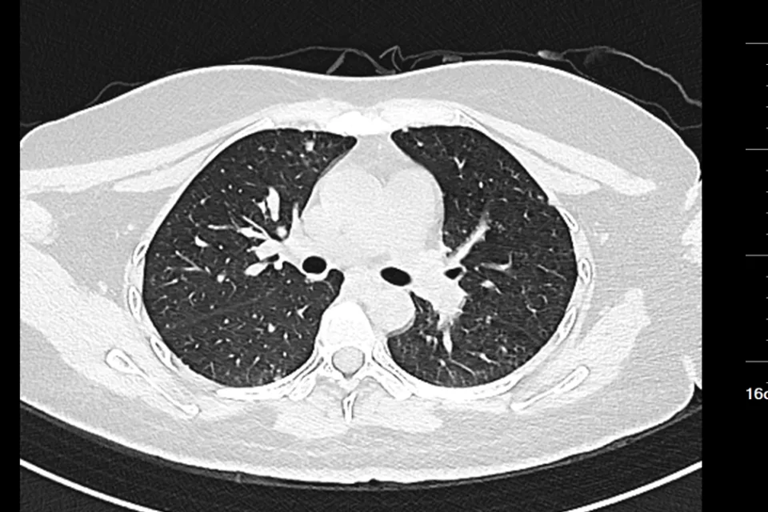

Hình ảnh chụp CT của nữ sinh 20 tuổi

Chụp CT cho thấy khối u đã di căn toàn thân, không còn chỉ định phẫu thuật. Các bác sĩ chỉ có thể đề nghị điều trị bằng hóa trị, xạ trị hoặc liệu pháp miễn dịch nhằm kiểm soát bệnh.